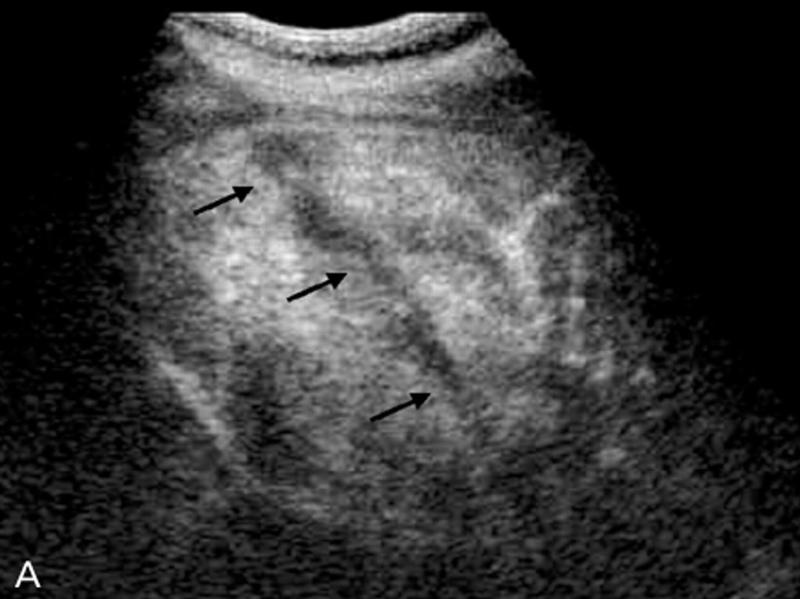

What is Metastatic disease?

This is the most common form of neoplastic involvement of the liver. The primary sites include colon, breast, and lung.

What is the sonographic appearance of Metastatic disease?

Appearance varies

Multiple nodes

Solitary

Well

defined

Echogenic to hypoechoic mass

Homogenous

Calcification

Necrosis

What are the presenting symptoms of Metastatic disease?

jaundice

hepatomegaly

weight loss

decreased appetite

What are the lab values that would suggest Metastatic disease?

Abnormal LFT